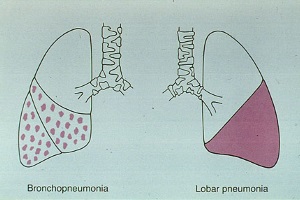

виды пневмонии

Пневмония – острое инфекционное заболевание, преимущественно бактериальной этиологии, характеризующееся очаговым поражением респираторных отделов лёгких с обязательным наличием внутриальвеолярной экссудации.